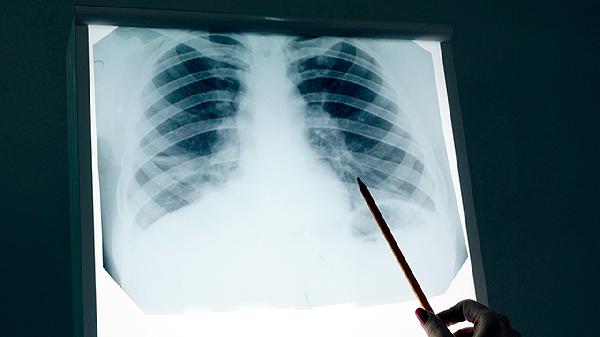

中医治疗肺癌强调整体调节,需全程配合现代医学诊疗。患者应定期复查影像学及肿瘤标志物,中药使用需避开放化疗敏感期。保持良好作息,避免风寒侵袭,情绪管理可通过五音疗法疏导。任何传统疗法实施前须经中西医肿瘤专科医师评估,禁止自行停用标准治疗方案。